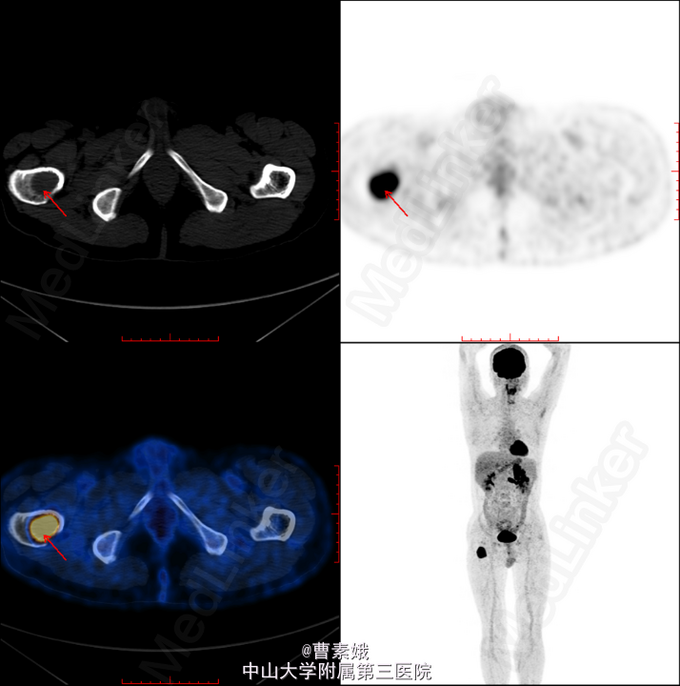

初步诊断:右股骨近端骨肿瘤(?)。 考虑右股骨肿物性质未明,遂于我院行全身PET/CT及腹部CT增强扫面,检查结果提示:1、左肾肿块并左肾静脉充盈缺损,代谢活跃,考虑左肾癌(透明细胞癌可能)并左肾静脉癌栓形成;双侧肾上腺座椅;腹膜后淋巴结转移;左侧股骨 经济股骨上段骨转移。随后患者行“左股骨肿物+左肾肿物穿刺活检术”,冰冻病理结果提示:左肾透明细胞癌,左股骨肿物考虑肾透明细胞癌转移。考虑患者肾透明细胞癌多发转移,无手术指征,转入肿瘤内科予索坦靶向治疗。